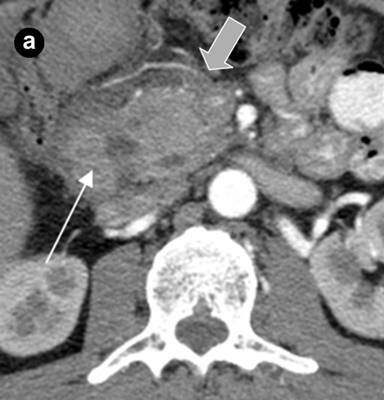

A 43-year-old man with abdominal pain of a one year duration, nausea, vomiting, weight loss and intermittent jaundice was referred to the Hospital of the Russian Federal Security Service, Moscow, Russia, with a clinical diagnosis of chronic pancreatitis. The patient had a history of previous extensive small bowel resection; one year previously he had been operated on for acute pancreatitis with abdominal draining and a cholecystectomy. The epigastrium was mildly sensitive on physical examination. The laboratory findings were normal, except for a slight increase in the bilirubin level (40 µmol/L; reference range: 3.5-19.0 µmol/L). Abdominal US showed diffuse changes of the liver and pancreas. On computed tomography (Figure 6) and magnetic resonance imaging (Figure 7), a thick-walled cystic lesion 4x4.5 cm which had infiltrated the medial wall of the second part of the duodenum was observed against the background of the minimally changed pancreatic structure with pancreatic and common bile duct dilation,. Endosonography revealed a solid and septated cystic lesion mainly located in the submucosa of the narrowed second portion of the duodenal wall.

Figure 6. Arterial phase of multi-detector computed tomography before (a.) and 6 months after (b.) the pancreas-preserving resection of the second portion of the duodenum with the jejunal interposition (Case #2). a. There is a septated cystic structure (thin arrow) in the medial duodenal wall with prominent inflammation and fibrosis around the duodenum and pancreatic head (thick arrow). b. Neoduodenum (thin arrow) and pancreatic head (thick arrow) without signs of inflammation or fibrosis. |